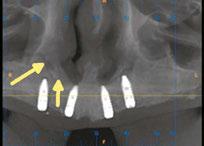

on the crest of the ridge in the region of teeth Nos. 15-25. While creating the incision, bleeding was noticed in the region of tooth No. 15 which intensified during the flap reflection (Figure 2). Bleeding was pulsatile, indicating an arterial bleed. Initially attempts to control bleeding included a pressure pack and ice pack, and the bleeder was isolated and the vessel ligated (Figure 3). The bleeding could be controlled, and the procedure was completed by placing four Bioner implants (Bioner, Spain), size 4/10 mm. Sutures were placed, and patient was kept on basic medication for pain and infection control. Immediately after the surgery, the patient was advised to get a CBCT. As shown in Figure 4, a coronal view and Figure 4B (yellow arrows), the position of the artery can be seen.

Figure 2 (left): Alveolar antral artery (AAA). Figure 3 (center): The artery has been ligated with suture. Figures 4A and 4B (right): CBCT post-implant placement and position of the artery coronally (top). 4B. Showing the position of alveolar antral artery (AAA) in relation to implant placement as indicated by the yellow arrows (bottom)